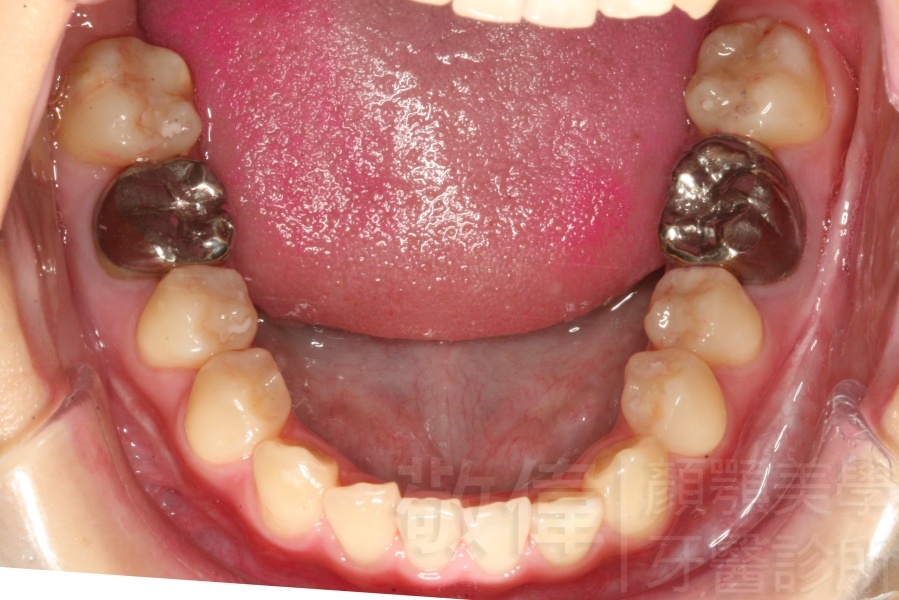

變臉矯正,原來戽斗妹跟大歪臉變成自信正妹

經由本院3D數影X光影像儀分析、與3D齒顎顏矯正技術,再配合口腔顎面正顎專科醫師施以正顎手術治療,雙方共同合作,使患者臉部外觀有很好的改善,大歪變小歪,產生了天南地北的大改變,她的人生也整個變得不一樣。

因為矯正與正顎手術的配合,使「戽斗妹」變成了「陽光正妹」,完全的改變了她的人生,在面對各種場合、與人交際都散發出自信微笑。所以,奉勸家長,如果小朋友有臉顎畸型的問題,應該考慮配合做這種簡單、安全、有效的正顎手術。